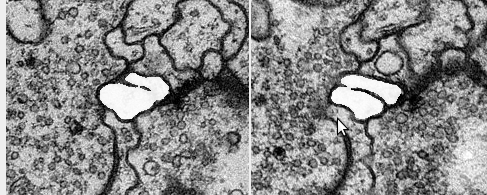

Use extremal value of outline curvature to discard slices and segments #4

Curvature